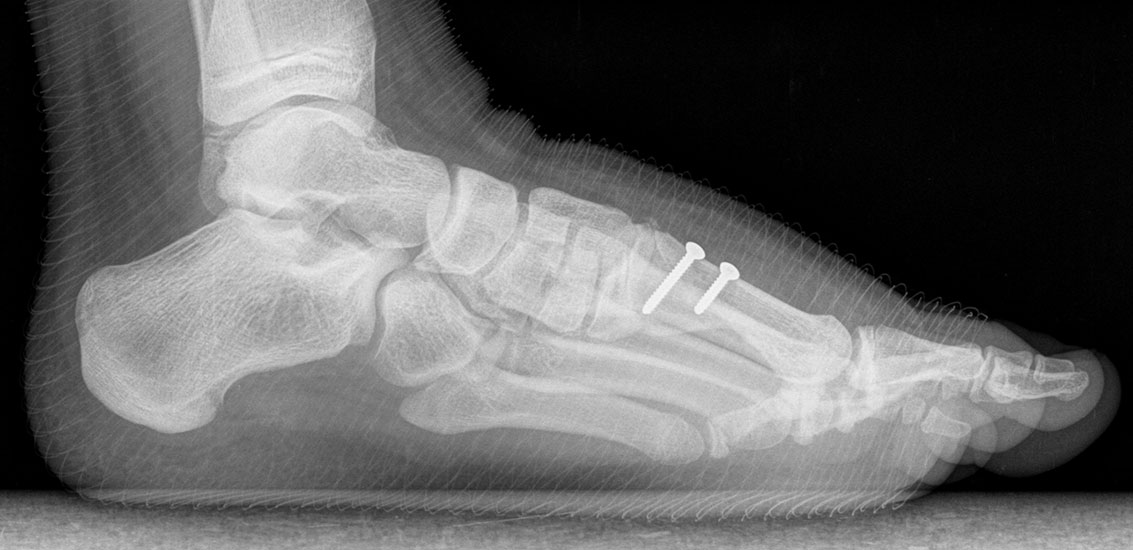

Röntgen

Standard ist die belastete Röntgenaufnahme des Fußes dorso-plantar und seitlich. Günstig ist eine Röhrenkippung von 10°-20°, um die Gelenke der Lisfranc-Linie einsehen zu können.

• Elevation/ Plantarisierung I. Strahl

• Pes metatarsus adductus